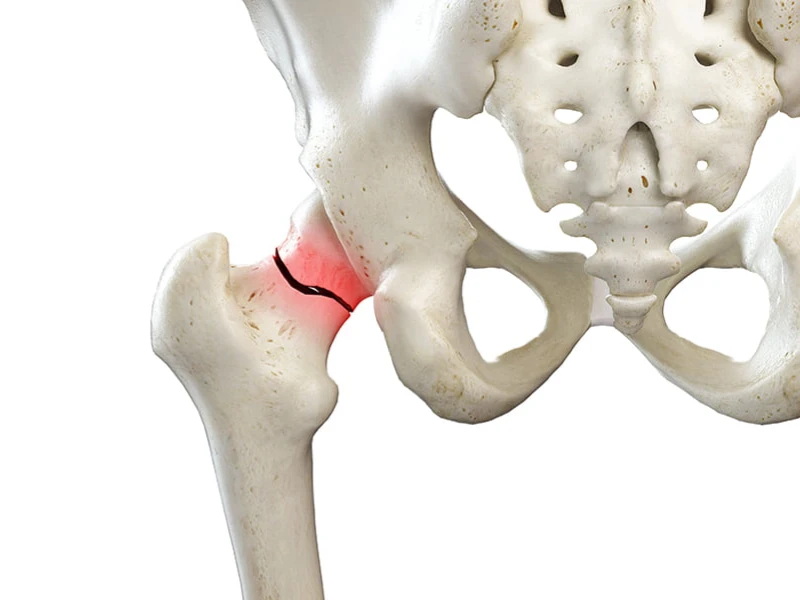

شکستگی لگن یکی از مهلک ترین شکستگیهای بدن انسان است. این نوع شکستگی نه تنها استخوان بدن، بلکه کل بدن

16 آگوست 2025